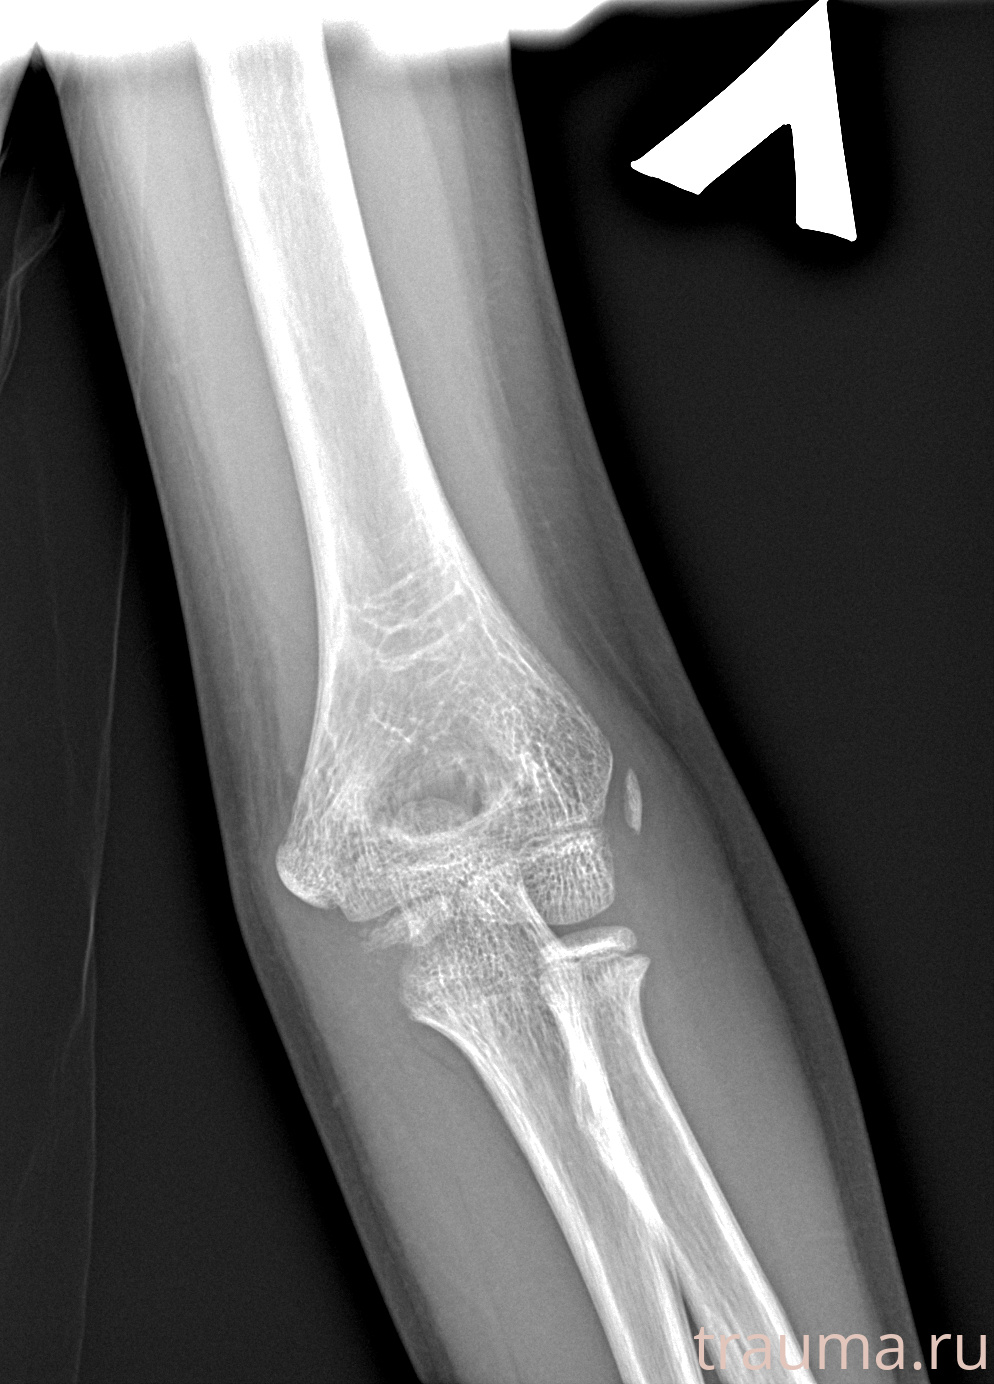

Рентгенограммы

Рентген на дому: по вашему адресу приезжает врач-рентгенолог, травматолог-ортопед с мобильным рентгеновским аппаратом, проводит диагностику травмы или заболевания, делает необходимые рентгенограммы, дает рекомендации по дальнейшему лечению. Получить качественные снимки в домашних условиях возможно благодаря уникальной методике, разработанной МосРентген Центром для института  Склифосовского